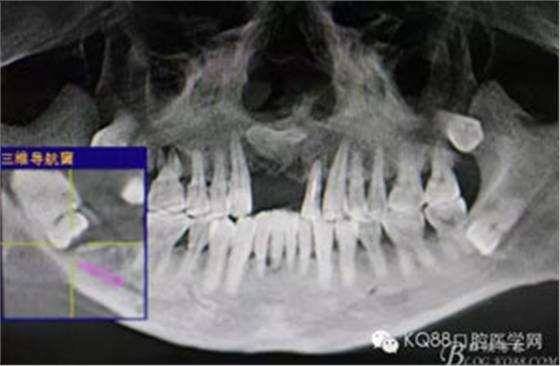

圖2.術(shù)前的CBC影像T檢查:48低位導(dǎo)致,近中牙尖緊鄰下頜神經(jīng)管。